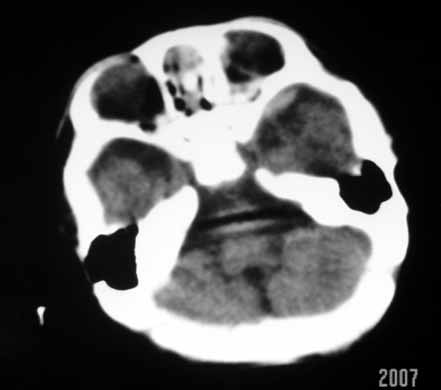

标题: PED0294: 2月婴儿.VitK缺乏症颅内出血.. [打印本页]

标题: PED0294: 2月婴儿.VitK缺乏症颅内出血..

可见 硬膜下及硬膜外血肿,蛛网膜下腔出血

以下是引用jiangjing在2007-8-2 15:07:00的发言:[br]可见 硬膜下及硬膜外血肿,蛛网膜下腔出血

vk缺乏症ct表现有脑实质内出血,珠网膜下腔,硬膜下出血,硬膜外出血,脑实质内出血少见。本病出血要点出血量大,多部位出血,脑室质出血呈团快状。